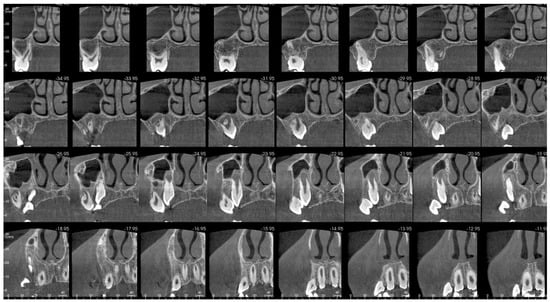

That finding necessitated further diagnostics with CBCT (Figure 4, Figure 5, Figure 6 and Figure 7). A 3D radiograph confirmed a round, well-demarcated, noninflammatory cyst-like lesion extending from Teeth 11 to 15.

Figure 5.

CBCT before treatment—axial view.

A hypodense focus representing a loss of osseous tissue surrounded the crown of the displaced upper right permanent canine. The unerupted first and second premolars were dislocated and rotated, and Tooth 12 also presented mesiorotation and mesioinclination. The teeth involved in the lesion had open apices and no sign of root resorption. The alveolar bone was deformed, especially in the vestibulopalatal dimension, with a noticeable displacement of the medial interior wall of the right maxillary sinus.